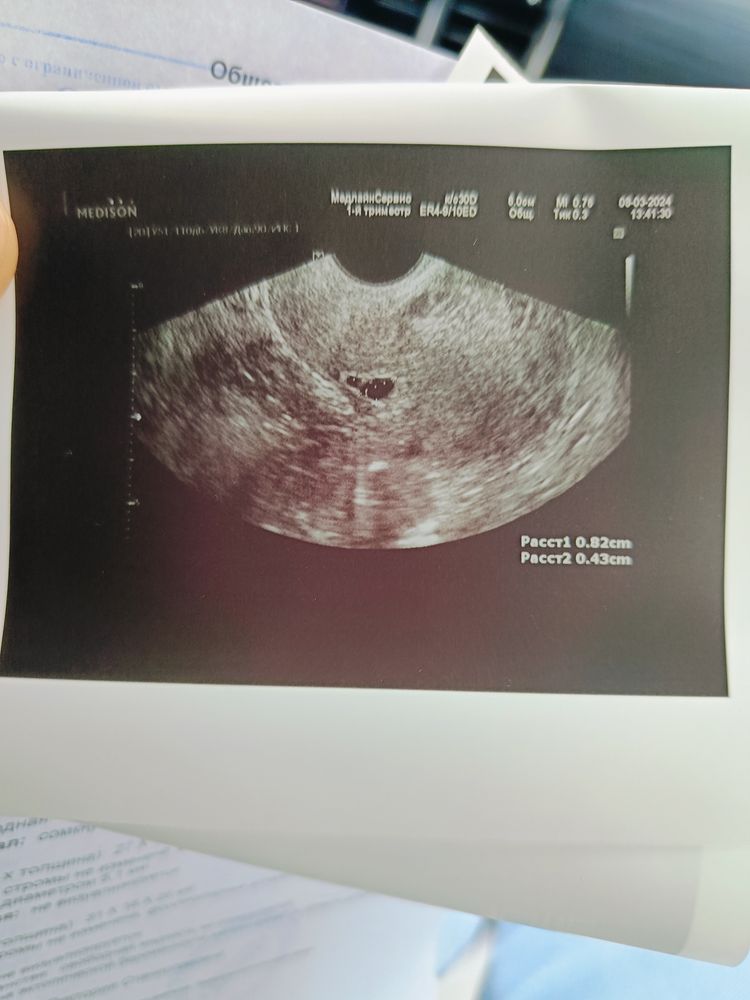

Да вот нашли вчера пя. Правда оно прикрепиоось неудачно